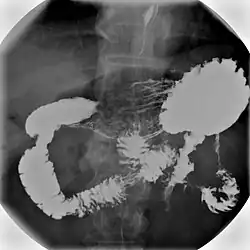

Normal barium swallow fluoroscopic image, showing the ingested barium sulfate being induced down the oesophagus by peristalsis. | |

An upper gastrointestinal series, also called a barium swallow, barium study, or barium meal, is a series of radiographs used to examine the gastrointestinal tract for abnormalities. A contrast medium, usually a radiocontrast agent such as barium sulfate mixed with water, is ingested or instilled into the gastrointestinal tract, and X-rays are used to create radiographs of the regions of interest. The barium enhances the visibility of the relevant parts of the gastrointestinal tract by coating the inside wall of the tract and appearing white on the film. This in combination with other plain radiographs allows for the imaging of parts of the upper gastrointestinal tract such as the pharynx, larynx, esophagus, stomach, and small intestine such that the inside wall lining, size, shape, contour, and patency are visible to the examiner. With fluoroscopy, it is also possible to visualize the functional movement of examined organs such as swallowing, peristalsis, or sphincter closure. Depending on the organs to be examined, barium radiographs can be classified into "barium swallow", "barium meal", "barium follow-through", and "enteroclysis" ("small bowel enema"). To further enhance the quality of images, air or gas is sometimes introduced into the gastrointestinal tract in addition to barium, and this procedure is called double-contrast imaging. In this case the gas is referred to as the negative contrast medium. Traditionally the images produced with barium contrast are made with plain-film radiography, but computed tomography is also used in combination with barium contrast, in which case the procedure is called "CT enterography".[1]